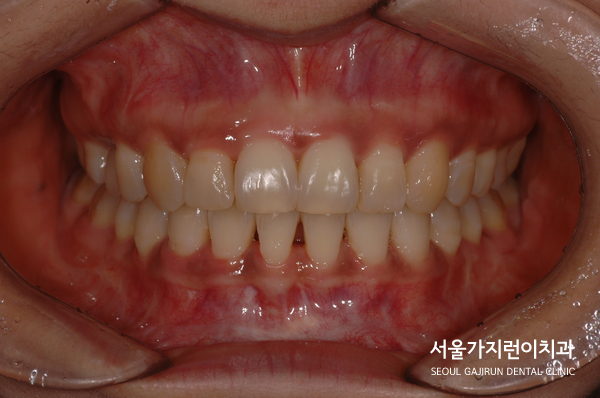

오늘은 과개교합 환자의 교정 케이스를 가져와봤습니다.

과개교합이란, 상악의 치아가 하악의 치아를 비정상적으로 덮은 교합 상태를 말합니다.

정면에서 봤을 때 윗니가 아랫니를 덮어 전혀 보이지 않는 상태였죠.

그래서 환자 분의 경우 기능적인 문제개선을 위해 교정치료를 진행했는데요.

다행히도 임플란트 이상 없이 교정력을 유지하면서 치아교정을 마무리할 수 있었습니다.